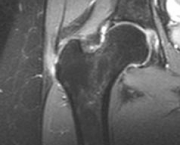

A bursite Trocanteriana é uma inflamação em uma ou mais bursas encontradas na articulação do quadril. Esta bursite pode ser causada por uma queda ou golpes ao lado do quadril, atrito associado a uso excessivo, pé pronado ou fraqueza de glúteo médio.

Um destes fatores presentes gerará a inflamação e consequente dor durante uma corrida, desajuste no andar da pessoa ou crepitação na articulação. O tratamento deve ser realizado conforme a causa da doença, por exemplo, se for por fraqueza de glúteo, deve-se fortalecer glúteo.